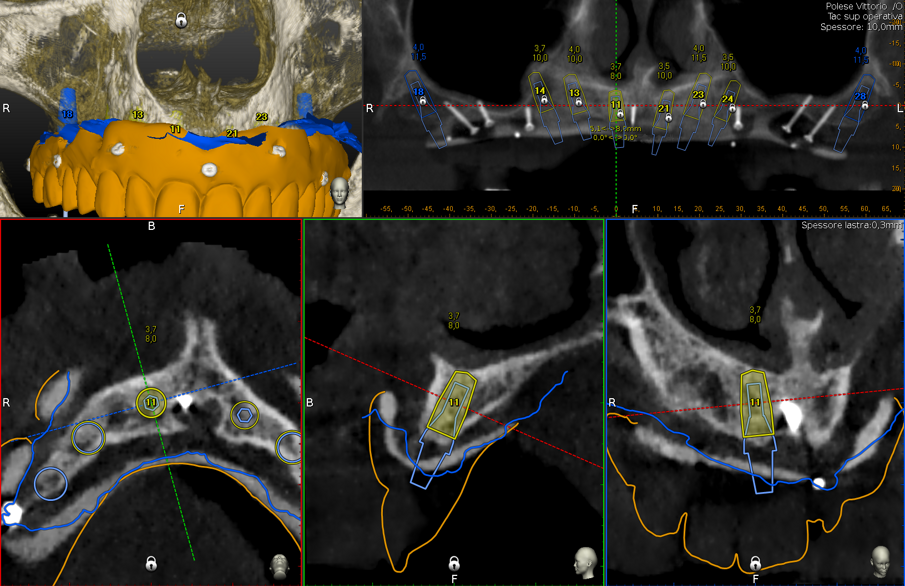

Inoltre l’aiuto della chirurgia navigata, consente di posizionare gli impianti in una posizione pianificata in precedenza ben distribuita lungo l’arcata, limitando al massimo i disparallelismi e semplificando le fasi protesiche.

Gli impianti vengono distribuiti lungo tutta l’arcata cercando il parallelismo e limitando il più possibile i cantilever (6-7 impianti superiori e 5-6 impianti inferiori). La scelta di utilizzare i monconi dritti (grazie al parallelismo degli impianti) è da preferire in quanto quest’ultimi sono anche i più robusti e resistenti nel tempo al carico assiale; inoltre caricano l’impianto lungo il suo asse limitando i carichi disassati. Una volta elevato il lembo mucoperiosteo ed evidenziato l’osso alveolare o basale, attenzione deve essere fatta nel fare un’ostectomia riduttiva mediante una fresa a palla del diametro di 0,6-0,8 cm per creare un piano più uniforme possibile tale da formare una piattaforma d’osso alla stessa altezza, guadagnando anche spessore V-L ed uniformità. Gli impianti devono essere posizionati alla stessa altezza tra di loro e distanziati in maniera tale da favorire le manovre di igiene orale inter-implantare. Una volta posizionate le fixture sottocrestali (1-3 mm) come descritto, vanno connessi i monconi solitamente con collare mucoso di 3-4,5 mm in altezza, ponendo particolare attenzione che i tessuti molli suturati non coprano la parte di accoppiamento conometrico. Verificato il parallelismo corretto dei monconi mediante i pin parallelizzatori, siamo certi che l’accoppiamento e la disconnessione delle cappette contenute nella protesi potrà avvenire nel miglior modo possibile senza creare tensioni.